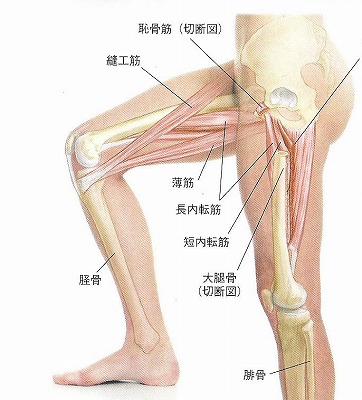

第1層(表層)は恥骨筋・薄筋・長内転筋の3つの筋肉があります。第2層(中間層)には短内転筋があります。第3層(深層)には大内転筋・小内転筋があります。これら3つの筋肉を内転筋群と言います。内転筋群に痛みを感じた場合、炎症を起こしている状態は内転筋群炎症になります。

炎症を起こしてしまう原因は色々あります。変形性股関節症、関節リウマチなど病気からくる場合、O脚やX脚など骨格の歪みからくるものになります。腰や足首、足の裏などの痛みをかばうことによっても炎症を起こしてしまうことがあります。症状としては太ももの内側の痛みになりますが、炎症を起こしている筋肉によって痛む場所が変わってきます。太ももの付け根あたりから膝の上あたりまで、筋肉の伸びる部位のどこかで痛みを感じます。